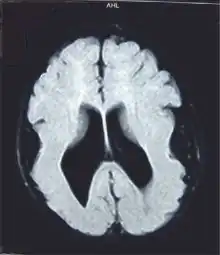

Cerebro con lisencefalia.

Resonancia magnética que muestra "cerebro liso"

La lisencefalia se puede diagnosticar durante o poco después del nacimiento. El diagnóstico se puede confirmar por ultrasonido, por tomografía computarizada (CT) o por resonancia magnética (MRI por su sigla en inglés).[1]